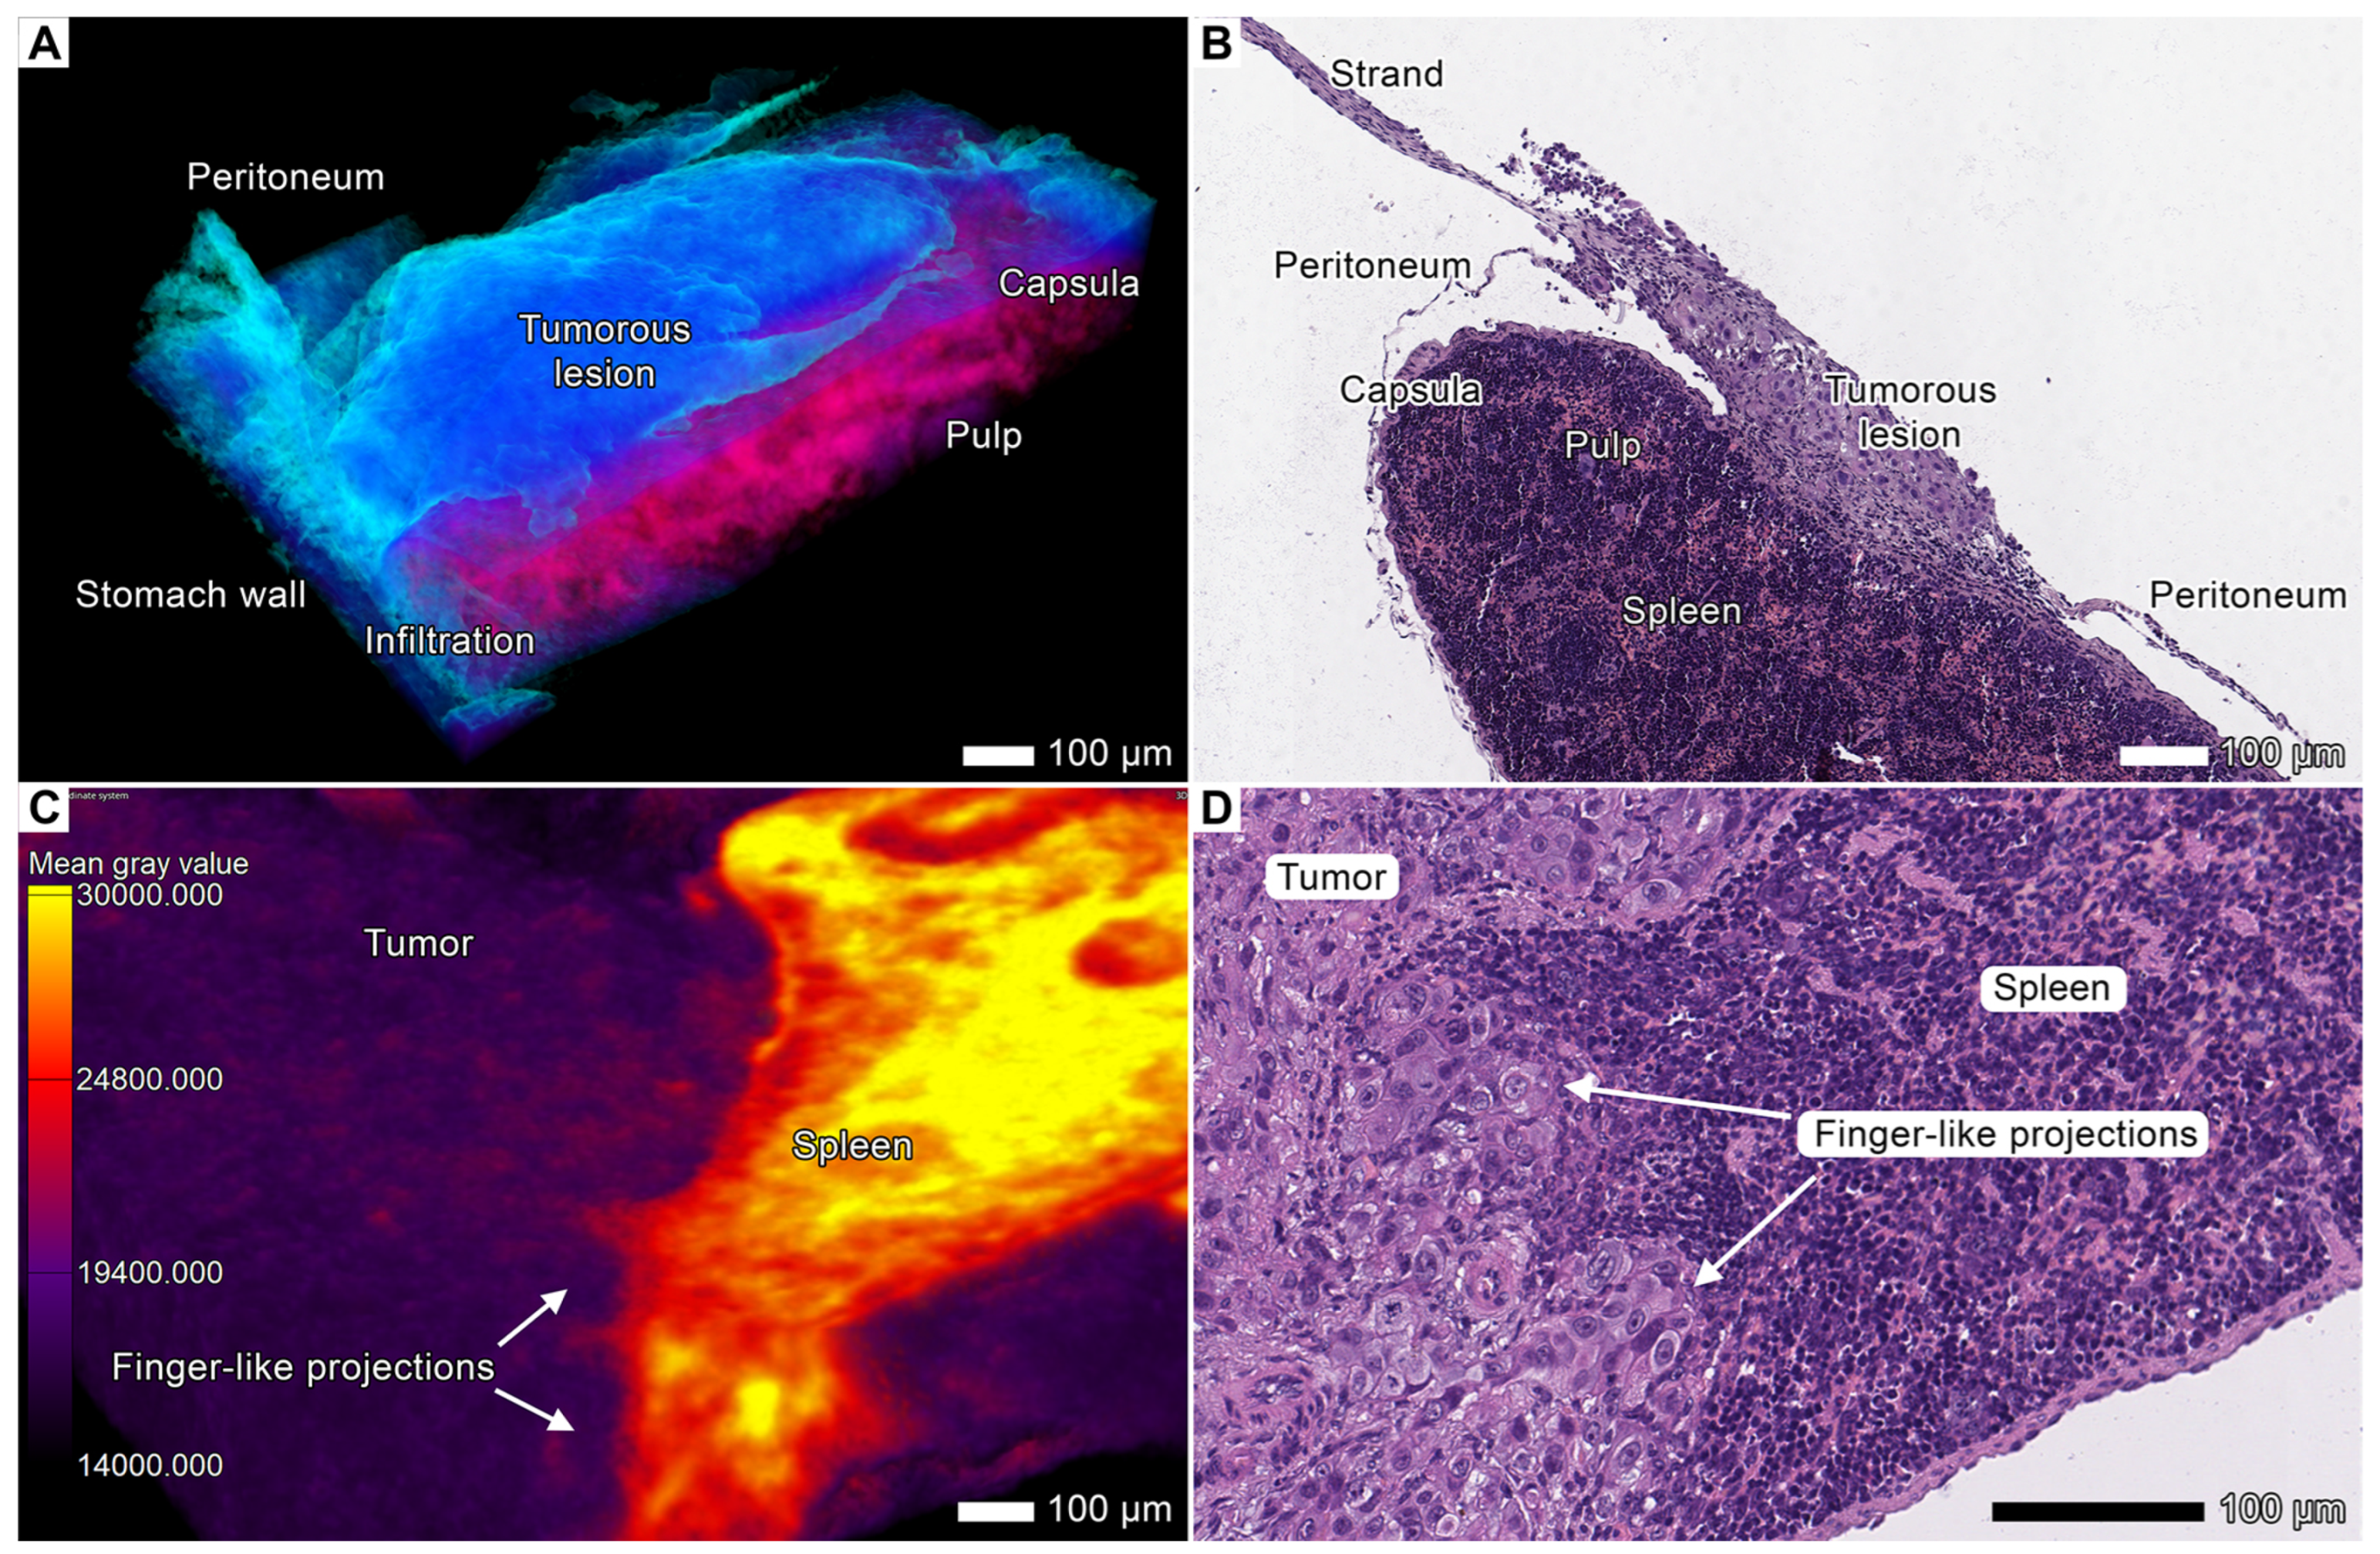

3.3. Tumor Invasion into the Spleen